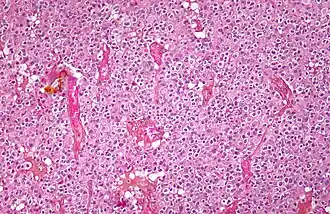

| Micrograph of an oligodendroglioma showing the characteristic branching, small, chicken wire-like blood vessels and fried egg-like cells, with clear cytoplasm and well-defined cell borders. H&E stain. | |

Oligodendrogliomas cannot currently be differentiated from other brain lesions solely by their clinical or radiographic appearance. As such, a brain biopsy is the only method of definitive diagnosis. Oligodendrogliomas recapitulate the appearance of the normal resident oligodendroglia of the brain. (Their name derives from the Greek roots 'oligo' meaning "few" and 'dendro' meaning "trees".) They are generally composed of cells with small to slightly enlarged round nuclei with dark, compact nuclei and a small amount of eosinophilic cytoplasm. They are often referred to as "fried egg" cells due to their histologic appearance (though, the perinuclear halo on permanent sections is an artifact of tissue drying; fresh tissue lacks this characteristic "fried egg" appearance). They appear as a monotonous population of mildly enlarged round cells infiltrating normal brain parenchyma and producing vague nodules. Although the tumor may appear to be vaguely circumscribed, it is by definition a diffusely infiltrating tumor.[6]

Classically they tend to have a vasculature of finely branching capillaries that may take on a "chicken wire" appearance. When invading grey matter structures such as cortex, the neoplastic oligodendrocytes tend to cluster around neurons exhibiting a phenomenon referred to as "perineuronal satellitosis". Oligodendrogliomas may invade preferentially around vessels or under the pial surface of the brain.[6]